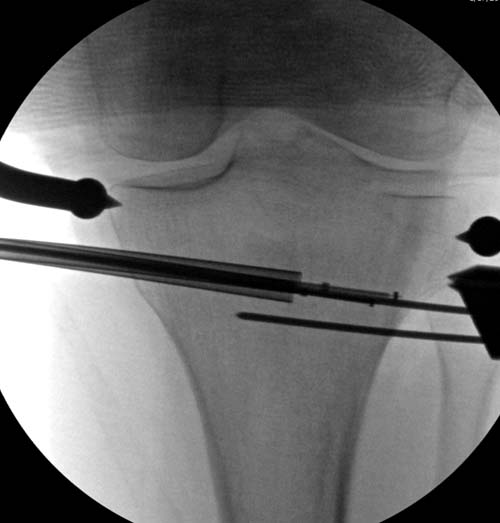

Для лечения некоторых видов центральной импрессии (Schatzker III) можно применить методику Balloon tibioplasty, которая позволяет приподнять сустав без дополнительных доступов. Для информации здесь недавний пример, дефект заполнен жидкой формой композитного материала PRO-DENSE: http://www.wmt.com/prodense/product_overview.asp